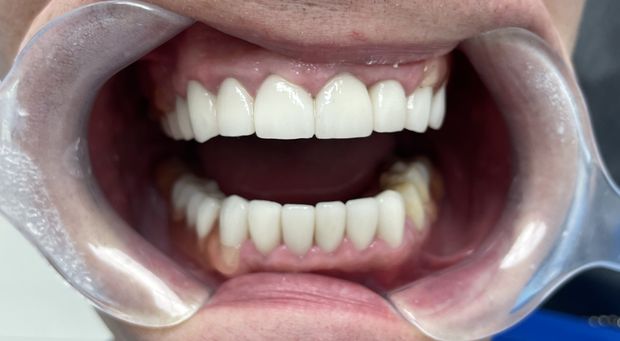

Pełna rekonstrukcja zgryzu, zmiana koloru i kształtu zębów za pomocą koron i mostów cyrkonowych licowanych porcelaną w kolorze BL2.